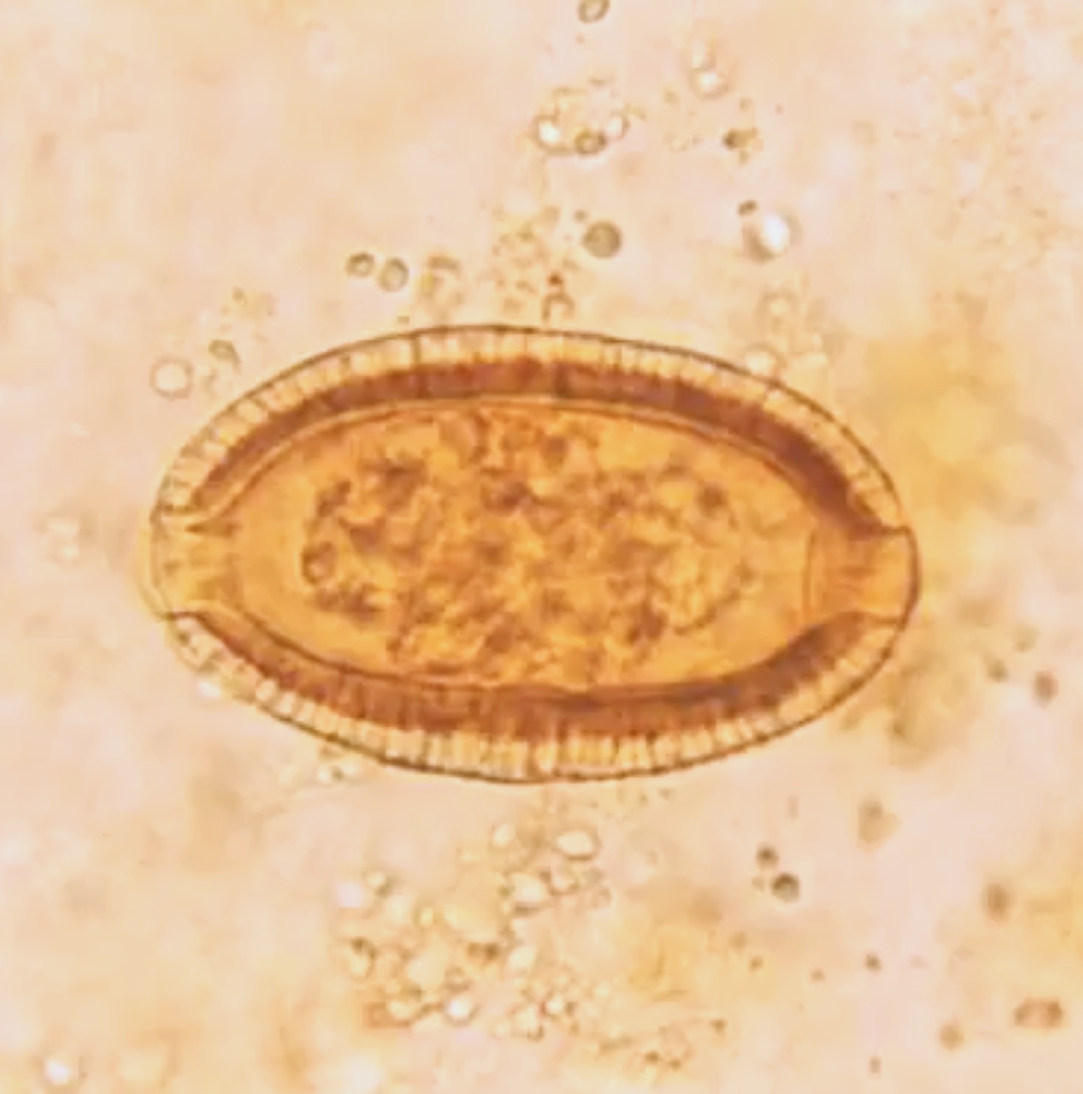

Trichuris ovis

Host: cattle, sheep, and goats; Location: cecum and colon; Common name: Whipworm; Clincal signs: dark feces, anorexia, and anemia; Treatment: benzimidazoles, probenzimidazoles, and ivermectin